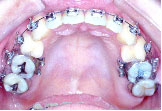

上あごは左へ2mm,前方へ2mm(Le Fort 1型)、下あごは右後方へ3.5mm,正面右へ3mm、左後方へ2.5mm(IVRO)、また顔のバランスをとるためあごの先を前方に5mm移動しました。(genioplasty)手術が終わり、退院当日にできるだけ来院していただきます。この方は手術後13日目でした。

手術前に製作して渡しておいた装置(オルソサージカルスプリント)を入れ、ゴムをかけた状態できていただきます。

術前矯正がうまくいったので術後矯正は微調整で済みました。

骨が固まり安定するまで待って装置をはずします。